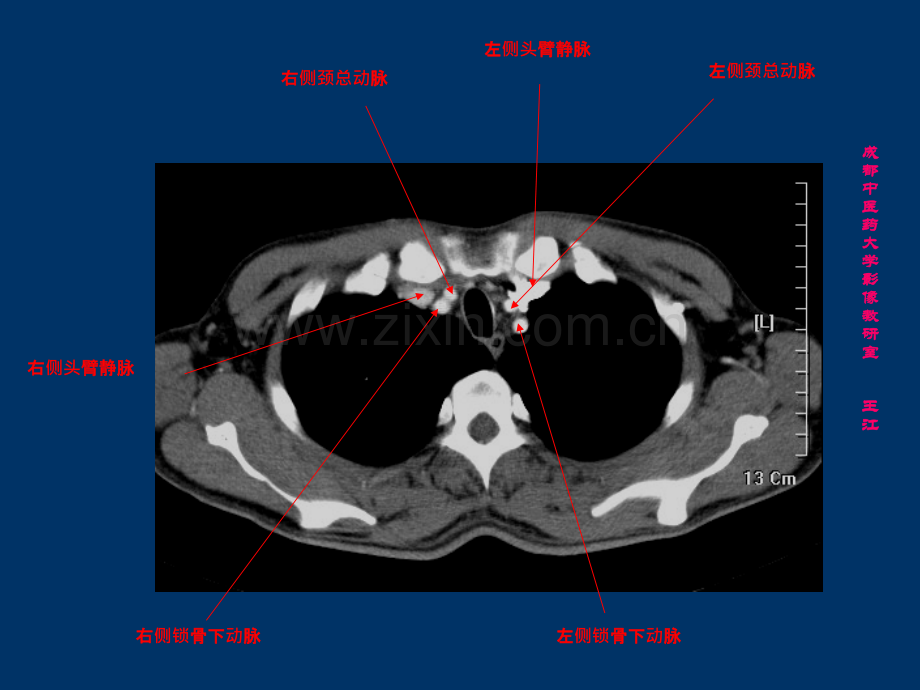

右右侧头臂静脉臂静脉左左侧头臂静脉臂静脉左左侧颈总动脉脉左左侧锁骨下骨下动脉脉右右侧颈总动脉脉右右侧锁骨下骨下动脉脉成成都都中中医医药药大大学学影影像像教教研研室室王王江江右右侧头臂静脉臂静脉左左侧头臂静脉臂静脉左左侧颈总动脉脉左左侧锁骨下骨下动脉脉头臂臂动脉脉成成都都中中医医药药大大学学影影像像教教研研室室王王江江左右左右侧头臂静脉臂静脉汇合区合区胸腺胸腺主主动脉弓脉弓成成都都中中医医药药大大学学影影像像教教研研室室王王江江上腔静脉上腔静脉气管气管食道食道奇静脉奇静脉成成都都中中医医药药大大学学影影像像教教研研室室王王江江左肺左肺动脉脉升主升主动脉脉降主降主动脉脉上腔静脉上腔静脉右主支气管右主支气管左主支气管左主支气管成成都都中中医医药药大大学学影影像像教教研研室室王王江江肺肺动脉主干脉主干左肺左肺动脉脉右肺右肺动脉脉上腔静脉上腔静脉成成都都中中医医药药大大学学影影像像教教研研室室王王江江右下肺右下肺动脉脉左下肺左下肺动脉脉升主升主动脉根部脉根部左心房左心房右心耳右心耳成成都都中中医医药药大大学学影影像像教教研研室室王王江江左心房左心房右心房右心房右肺静脉右肺静脉左肺静脉左肺静脉成成都都中中医医药药大大学学影影像像教教研研室室王王江江左心房左心房右心房右心房右心室右心室左心室左心室降主降主动脉脉成成都都中中医医药药大大学学影影像像教教研研室室王王江江降主降主动脉脉下腔静脉下腔静脉食道食道成成都都中中医医药药大大学学影影像像教教研研室室王王江江隔隔顶奇静脉奇静脉食道食道下腔静脉下腔静脉成成都都中中医医药药大大学学影影像像教教研研室室王王江江膈肌脚膈肌脚成成都都中中医医药药大大学学影影像像教教研研室室王王江江